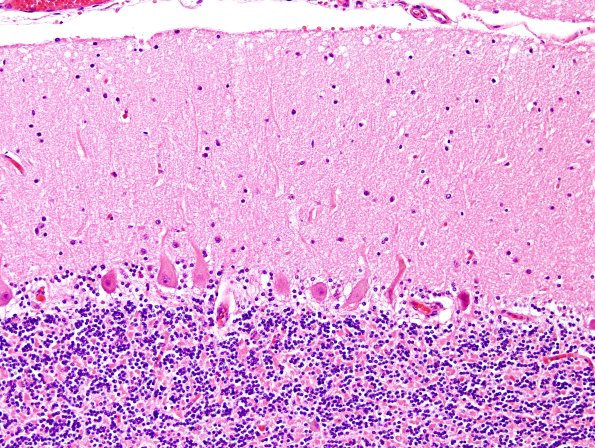

Neuronal Ceroid Lipofuscinosis (NCL)

2H1,2 Purkinje cells are well preserved but contain lipopigment. (H&E)